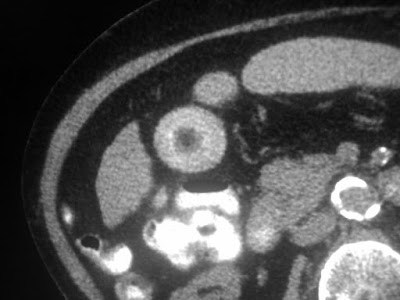

A beautiful round gall stone

A beautiful gall stone!